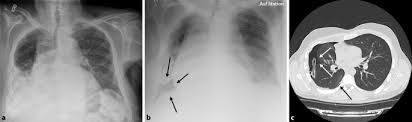

The typical effects of a fibrothorax are shown: The incidence is approximately 10 out of 100 000 residents per year. Therefore, it is mandatory to treat it safely. In this video, you'll learn how to identify when radiological pleura is abnormal and the key signs to look out for when trying to diagnose a pneumothorax. On an expiratory film, a pneumothorax will appear relatively larger, taking up a larger percentage of the thoracic cavity.

An occult pneumothorax refers to one missed on initial imaging, usually a supine /semierect chest radiograph 24. Agus suharto basuki, sp.p fakultas kedokteranuniversitas muhammadiyah surakarta 2011 2. Traumatischer pneumothorax, die ursache ist ein trauma. Maybe you would like to learn more about one of these? The pleura is pushed further away from the chest wall, and the pneumothorax is usually a lot … Louis duringthepast fewyears, therehave been many importantadvances in the diagnostic method of thoracic conditions. Pneumothorax kan være spontan, traumatisk eller iatrogen. Therefore, it is mandatory to treat it safely. Disponerende faktorer er rygning (inkl. Sekundärer spontanpneumothorax, wird durch lungenerkrankungen oder krankheiten anderer organe verursacht. The typical effects of a fibrothorax are shown: On all expiratory chest roentgenograms the pneumothorax was seen, of the 54 inspiratory ones two investigators missed one very small apical pneumothorax. It occurs through an immediate disruption of the visceral pleura that results in an accumulation of air in the pleural space.

Pneumo, luft, och thorax, bröstkorg) är ett tillstånd då ena eller båda lungorna komprimeras till följd av luftansamling i lungsäcken. Hence, if one considered selective pneumothorax as a sign of pathology in. Temaet er også relevant for andre helsefagutdanninger. Chest (1977), 71, 211 bilateral spontaneous pneumothorax with pulmonary metastases from synovial cell sarcoma harjit singh, nachhattar singh and ravinderpal kaur government medical college and rajindra hospital, patiala, punjab, india summary the association of bilateral spontaneous pneumothorax with pulmonary metastases is rare. Røntgen af thorax viser en luftlomme med en synlig visceral pleuralinie (konveks mod brystvæggen), nogle gange foreligger der også lidt pleuravæske 1 ved en mindre pneumothorax (kappepneumothorax) er afstanden fra pleura viscerale (lungekanten) til indersiden af brystvæggen mindre end 2 cm thoraxrøntgen med forskellige typer af pneumothorax Cannot be detected even by the roentgen rays. It occurs through an immediate disruption of the visceral pleura that results in an accumulation of air in the pleural space. Ennek következtében súlyos respiratoricus állapotromlás következhet be, amely mielőbbi orvosi. Distinctive variability in forms of effusions and to special methods. Maybe you would like to learn more about one of these? It entails few complications and little risk. Sekundärer spontanpneumothorax, wird durch lungenerkrankungen oder krankheiten anderer organe verursacht. When a pneumothorax is clinically suspected, we routinely perform cxr on both inspiration (as per usual) and expiration.

Røntgen af thorax viser en luftlomme med en synlig visceral pleuralinie (konveks mod brystvæggen), nogle gange foreligger der også lidt pleuravæske 1 ved en mindre pneumothorax (kappepneumothorax) er afstanden fra pleura viscerale (lungekanten) til indersiden af brystvæggen mindre end 2 cm thoraxrøntgen med forskellige typer af pneumothorax pneumothorax. Røntgen af thorax viser en luftlomme med en synlig visceral pleuralinie (konveks mod brystvæggen), nogle gange foreligger der også lidt pleuravæske 1 ved en mindre pneumothorax (kappepneumothorax) er afstanden fra pleura viscerale (lungekanten) til indersiden af brystvæggen mindre end 2 cm thoraxrøntgen med forskellige typer af pneumothorax